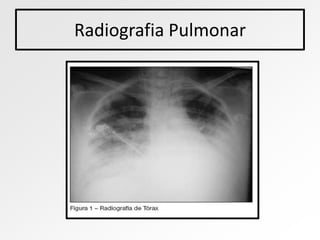

• Radiografia de tórax pode mostrar o acúmulo de líquidos no pulmão

Radiografia Pulmonar

• Raio X, nos casos de EPA deve aparecer partes

“esbranquiçadas”, indicando o acumulo de liquido.